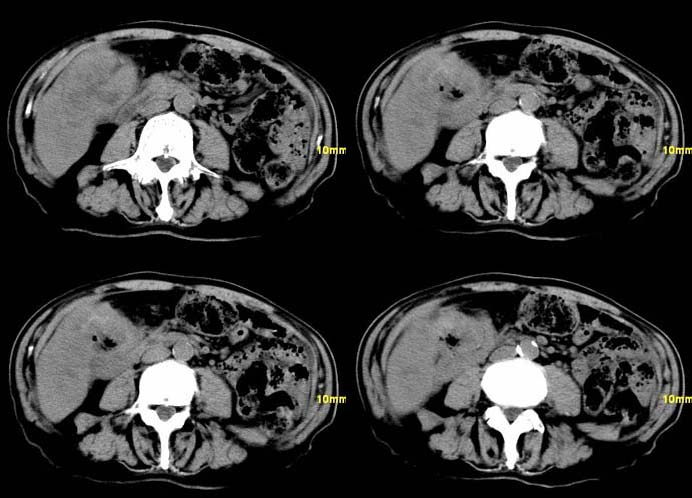

以下是引用余辉在2007-12-6 22:23:00的发言:[br]胆囊内多枚结石影,胆管全程扩张,右肝内病灶强化符合脓肿表现现(左肝病灶图像未传完),考虑急性梗阻性化脓性胆囊胆管炎合并肝多发脓肿(建议补传左肝病灶图像)